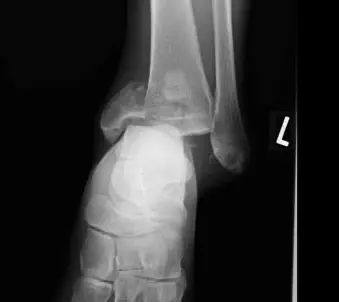

46歳男性、既往歴特記すべき事項なし。バイクを20~30km/hで運転中に乗用車の側面に接触して転倒受傷し、当院救急外来に搬送となった。

身体所見

左足関節に変形と内側に著しい腫脹・圧痛を認めた。単純レントゲン像(左下腿正面像)で左脛骨関節内骨折と関節軟骨の陥没所見を認め、CTにて脛骨関節面は粉砕し、脛骨天蓋部の骨軟骨片は20mm程度中枢へ転位していた(Muller AO分類43-C3、ピロン骨折:Ruedi分類gradeⅢ)。